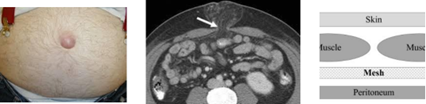

Vad menas med sublay-teknik?

A

• Bukhålan som en hink… Plåster inifrån kommer att hållas på plats av vattnet. Plåster utifrån trycks bort av vattnet. Nät under fascia/muskulatur (Sublay) kommer att hållas på plats av Buktrycket men större risk för recidiv om nätet ligger utanpå fascia/muskel (Onlay). (Framför peritoneum eller bakre rektusskida ovanför naveln).

• Grundprincip för operation av alla bukväggsbråck: Reponera in bråcksäck med innehåll i bukhålan Placera ett nät så att det inte ligger emot bukinnehåll och som täcks av fascia/muskel (Sublay).